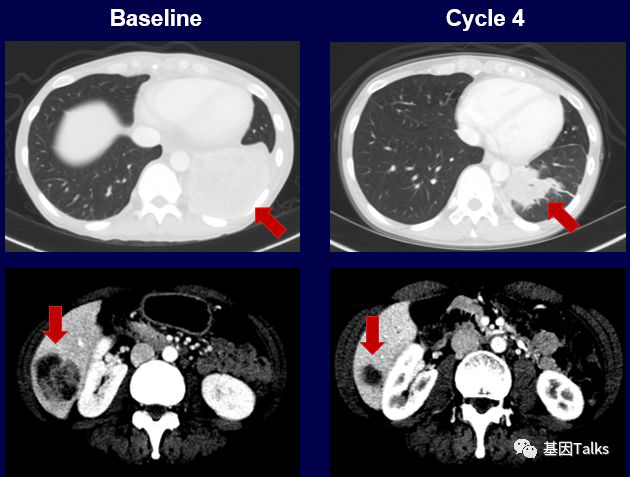

(1)1例肺癌合并SQSTM1-NTRK1融合:

(2)1例婴儿纤维肉瘤合并ETV6-NTRK3融合:

(3)1例分泌性乳腺癌合并ETV6-NTRK3融合:

上图下半部分显示治疗2周后,新发的耐药突变位点G595R已经检测不到,到现在治疗已经6个月了,治疗效果依然很好,未见有新的耐药位点出现。LOXO-195已经被FDA批准正式召开临床试验,耐药患者有了新希望。